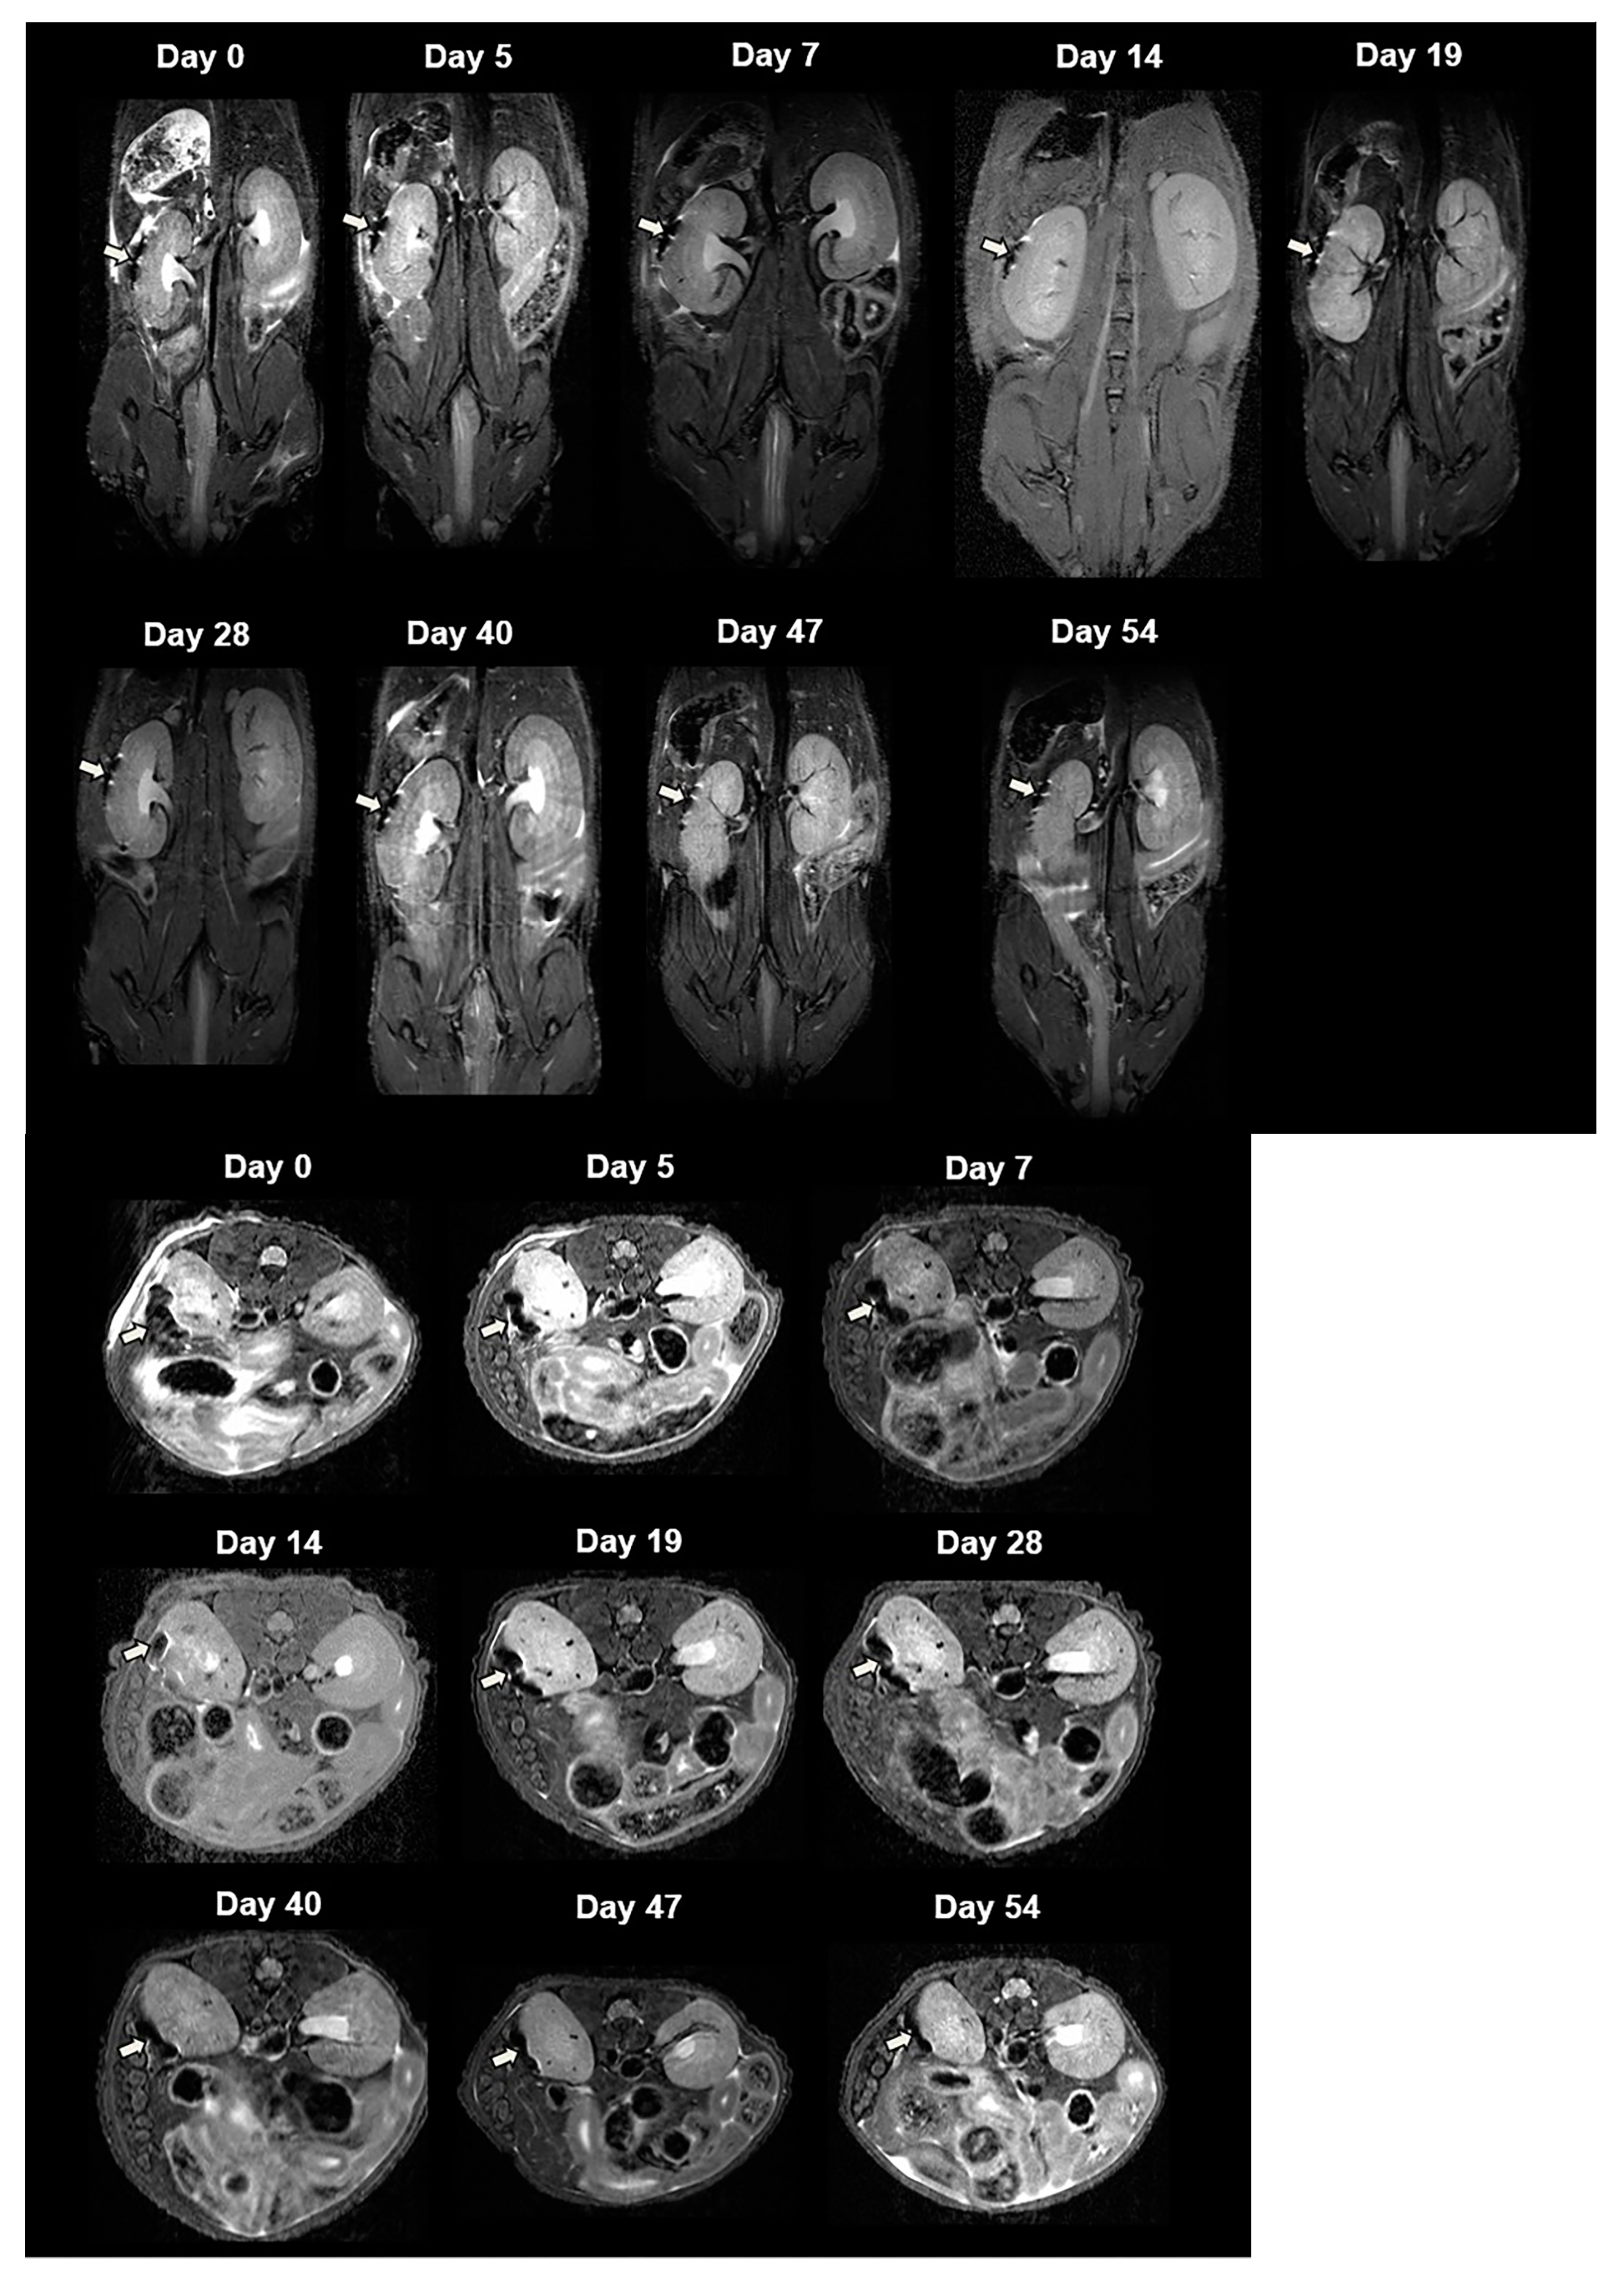

For in vivo MRI, we transplanted 2000 CSPIO-labeled NPCCs under the left kidney capsule of each nude mouse. Three recipients were scanned by a 7.0 T MRI system for up to 54 days. As shown in Figure 3, the graft of CSPIO-labeled NPCCs (indicated by arrows) was visualized as a distinct hypointense area on MR images located at the implantation site between day 0 and 54. This is expected, as we previously visualized CSPIO-labeled islets under mouse kidney capsules on MR scans as persistent hypointense areas after syngeneic and allogeneic transplantation [40,41,42]. The quantification analysis revealed that the MR signal intensity of the graft on the left kidney was significantly reduced compared to the mirror area on the right kidney at all time points (p = 0.000) (Figure 4). Previously, we observed that the MR signal loss was 20% lower in 200 CSPIO-labeled islet isografts than that of unlabeled islet isografts, and this difference persisted for 6 weeks [40]. In this study, 2000 CSPIO-labeled NPCC grafts made a persistent 60–80% reduction of MR signal for 54 days as compared to the same area in the contralateral kidney. To the best of our knowledge, we are the first to use MRI for the detection and monitoring of NPCC grafts.

Figure 3.

In vivo MR image of NPCCs after transplantation. Two thousand CSPIO-labeled NPCCs were transplanted under the left kidney capsule of a nude mouse. The recipient was scanned by a 7.0 T MRI system with coronal (upper panel) and transverse (lower panel) sections. The graft of CSPIO-labeled NPCCs was indicated by arrows.